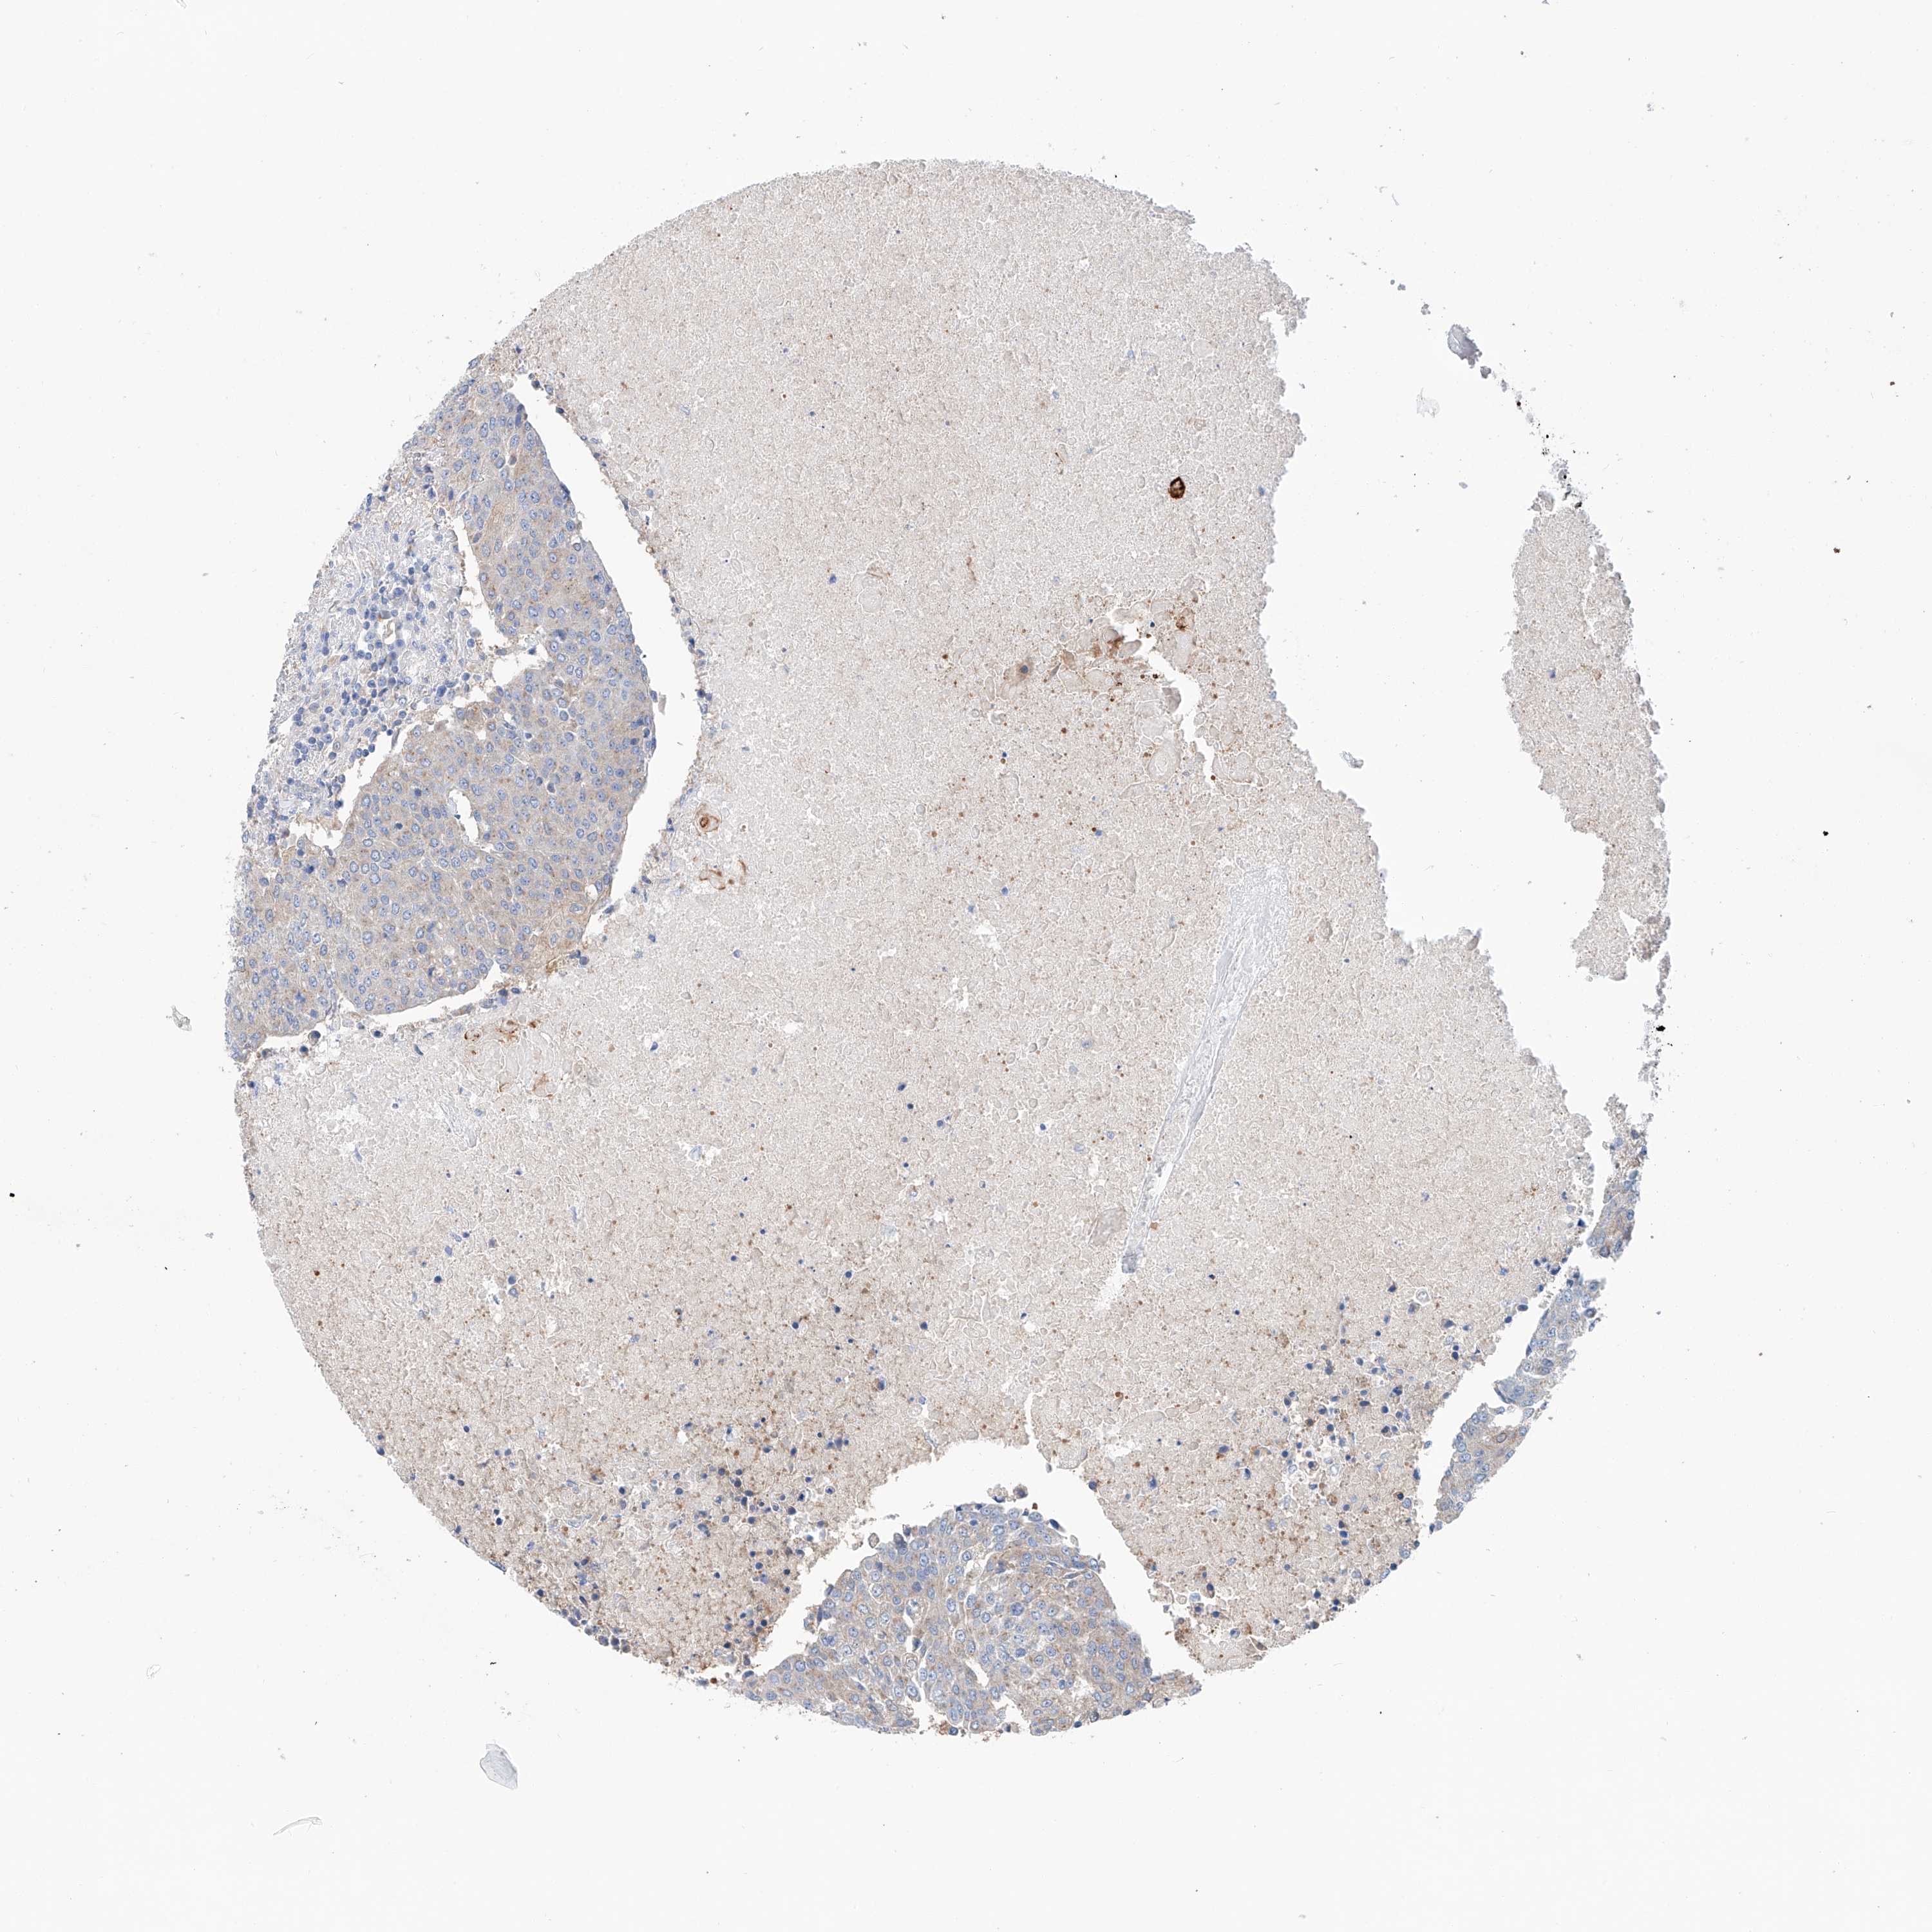

UROTHELIAL CANCER - Protein expressioni

A mouse-over function shows sample information and annotation data. Click on an image to view it in a full screen mode. Samples can be filtered based on level of antibody staining by selecting one or several of the following categories: high, medium, low and not detected. The assay and annotation is described here.

Note that samples used for immunohistochemistry by the Human Protein Atlas do not correspond to samples in the TCGA dataset.

Antibody stainingi

Antibody staining in the annotated cell types in the current human tissue is reported as not detected, low, medium, or high, based on conventional immunohistochemistry profiling in selected tissues. This score is based on the combination of the staining intensity and fraction of stained cells.

Each image is clickable and will lead to virtual microscopy that enables deeper exploration of all samples and also displays staining intensity scores, fraction scores and subcellular localization as well as patient and tissue information for each sample.

Antibody HPA030220

Staining

High

Medium

Low

Not detected

Intensity

Strong

Moderate

Weak

Negative

Quantity

>75%

75%-25%

<25%

None

Location

Nuclear

Cytoplasmic/membranous

Cytoplasmic/membranous,nuclear

Urothelial carcinoma, Low grade

Urothelial carcinoma, High grade